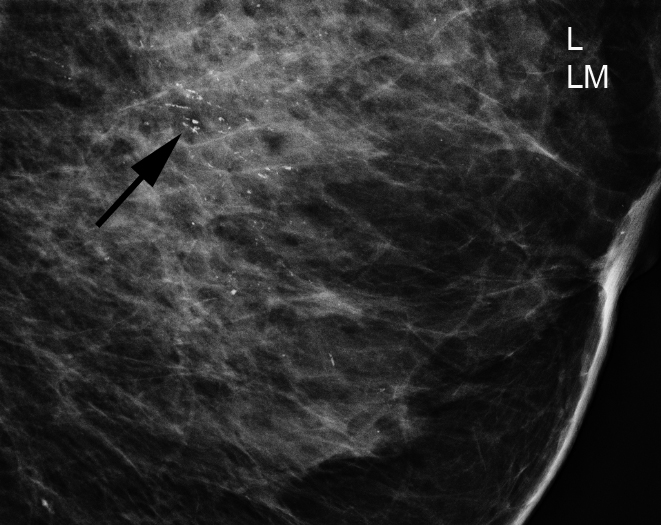

Brustkrebs ist die häufigste Krebserkrankung bei Frauen. Systematische Früherkennung soll die Sterblichkeit an Brustkrebs senken. Deshalb wurde in Deutschland seit 2005 das Mammographie-Screening-Programm aufgebaut, um bundesweit jeder Frau zwischen dem 50. und 69. Lebensjahr eine qualitätskontrollierte Brustkrebs-Früherkennung anzubieten.

Mit Hilfe des Landeskrebsregisters Nordrhein-Westfalen wurden 53.375 Untersuchungen aus der Zeit der Einführung des Mammographie-Screening-Programms hinsichtlich der Feststellung von Brustkrebs im Screening und im nachfolgenden zweijährigen Intervall nach unauffälliger Screening-Untersuchung ausgewertet. Aus den Daten wurde die Erkennungsrate invasiver Mammakarzinome durch die Früherkennungsuntersuchung und während des nachfolgenden zweijährigen Intervalls ermittelt. Basierend auf immunhistochemischen Untersuchungen, der Bestimmung von Hormonrezeptoren und des Her2-neu-Status, wurden Subgruppen hinsichtlich der Tumoraggressivität gebildet: Her2 -positive und triple-negative Mammakarzinome wurden als aggressiv definiert.

Die detaillierte Analyse der aggressiven Mammakarzinome zeigt unter Hormonrezeptor-negativen und Her2-positiven Karzinomen sechsfach höhere und unter triple-negativen Karzinomen zweifach höhere Erkennungsraten im Screening als im Intervall. Aggressive invasive Mammakarzinome werden mit der höchsten Rate unter 60 - bis 69-jährigen Frauen im Screening diagnostiziert. Die Stadien-Verteilung der aggressiven invasiven Mammakarzinome ist im Screening günstiger als im Intervall.

Nach den Analysen ermöglicht das Mammographie-Screening offensichtlich eine frühzeitigere Diagnose auch der aggressiven Tumorsubtypen. Diese Erkrankungsgruppe ist bei Frauen ab dem 60. Lebensjahr häufiger als bei Frauen zwischen 50 und 59 Jahren. „Die Ergebnisse sind ein weiterer Beleg, dass eine systematische Brustkrebs-Früherkennung Sinn macht“, erläutert Prof. Dr. Walter Heindel vom Referenzzentrum für Mammographie des Universitätsklinikums Münster.